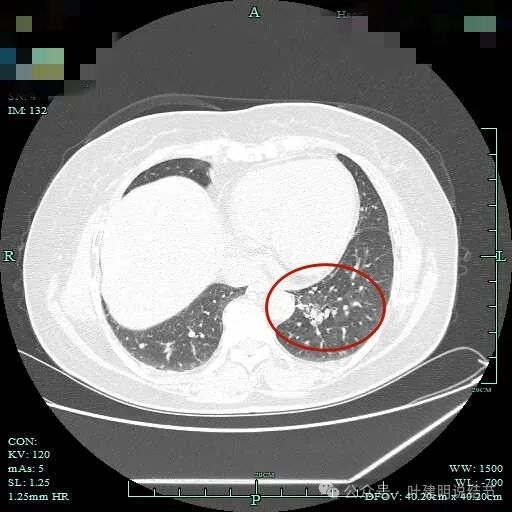

病灶轮廓欠清,较为散在,缺乏聚拢性,似乎有些像斑点状。

有少许磨玻璃成分出现,较前面层面整体轮廓显得清楚点。